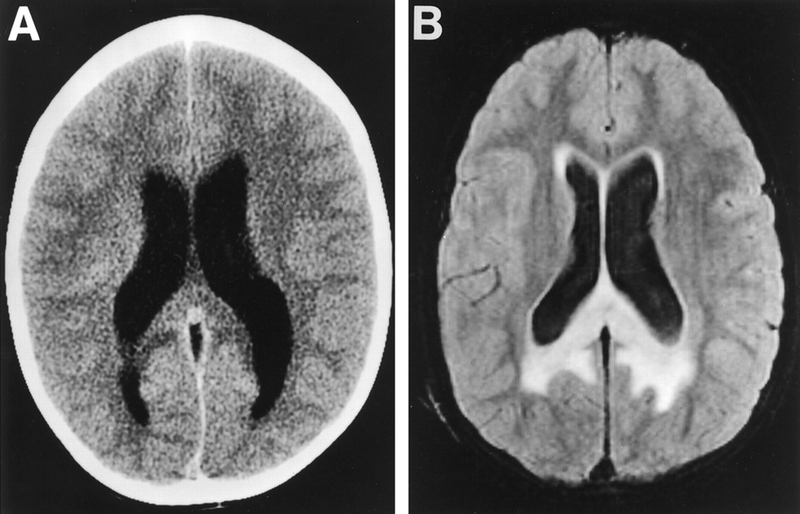

Chẩn đoán não úng thủy

Khi đứng trước một trường hợp nghi ngờ não úng thủy, bác sĩ sẽ đánh giá kỹ lưỡng lâm sàng người bệnh bao gồm hỏi về tiền sử bệnh lý bản thân, gia đình, quá trình diễn biến bệnh lần này và thực hiện các động tác thăm khám để đưa ra các chỉ định phù hợp tiếp theo.

Các cận lâm sàng để đánh giá chức năng của thần kinh trung ương, chẩn đoán nguyên nhân, chẩn đoán xác định bệnh thường được lựa chọn bao gồm:

• Chụp cắt lớp vi tính (CT).

• Chụp cộng hưởng từ (MRI).